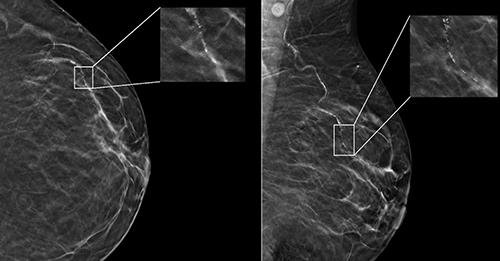

AGE, RACE IMPACT AI PERFORMANCE ON DIGITAL MAMMOGRAMS

In a study of nearly 5,000 screening mammograms interpreted by an FDA-approved AI algorithm, patient characteristics such as race and age influenced false positive results. The study’s results were published in Radiology, a journal of the Radiological Society of North America (RSNA).

“AI has become a resource for radiologists to improve their efficiency and accuracy in reading screening mammograms while mitigating reader burnout,” said Derek L. Nguyen, M.D., assistant professor at Duke University in Durham, North Carolina. “However, the impact of patient characteristics on AI performance has not been well studied.”

Nguyen said while preliminary data suggests that AI algorithms applied to screening mammography exams may improve radiologists’ diagnostic performance for breast cancer detection and reduce interpretation time, there are some aspects of AI to be aware of.

“There are few demographically diverse databases for AI algorithm training, and the FDA does not require diverse datasets for validation,” he said. “Because of the differences among patient populations, it’s important to investigate whether AI software can accommodate and perform at the same level for different patient ages, races and ethnicities.”

In the retrospective study, researchers identified patients with negative (no evidence of cancer) digital breast tomosynthesis screening examinations performed at Duke University Medical Center between 2016 and 2019. All patients were followed for a two-year period after the screening mammograms, and no patients were diagnosed with a breast malignancy.

The researchers randomly selected a subset of this

group consisting of 4,855 patients (median age 54 years) broadly distributed across four ethnic/racial groups. The subset included 1,316 (27%) white, 1,261 (26%) Black, 1,351 (28%) Asian, and 927 (19%) Hispanic patients.

A commercially available AI algorithm interpreted each exam in the subset of mammograms, generating both a case score (or certainty of malignancy) and a risk score (or one-year subsequent malignancy risk).

“Our goal was to evaluate whether an AI algorithm’s performance was uniform across age, breast density types and different patient race/ethnicities,” Nguyen said.

Given all mammograms in the study were negative for the presence of cancer, anything flagged as suspicious by the algorithm was considered a false positive result. False positive case scores were significantly more likely in Black and older patients (71-80 years) and less likely in Asian patients and younger patients (41-50 years) compared to white patients and women between the ages of 51 and 60.

“This study is important because it highlights that any AI software purchased by a health care institution may not perform equally across all patient ages, races/ ethnicities and breast densities,” Nguyen said. “Moving forward, I think AI software upgrades should focus on ensuring demographic diversity.”

Nguyen said health care institutions should understand the patient population they serve before purchasing an AI algorithm for screening mammogram interpretation and ask vendors about their algorithm training.

“Having a baseline knowledge of your institution’s demographics and asking the vendor about the ethnic and age diversity of their training data will help you understand the limitations you’ll face in clinical practice,” he said.